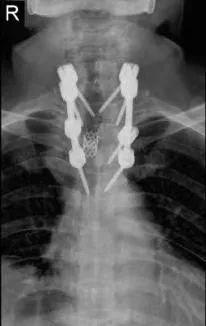

经郑州大学附属郑州中心医院脊柱转移癌专家团队会诊,决定为王爷爷进行手术+放疗等综合治疗。

手术在全麻下进行两小时取得圆满成功,手术当天王爷爷疼痛就消失了,下肢瘫痪也明显改善。

术后

现在王爷爷不仅不痛了,还能正常行走。